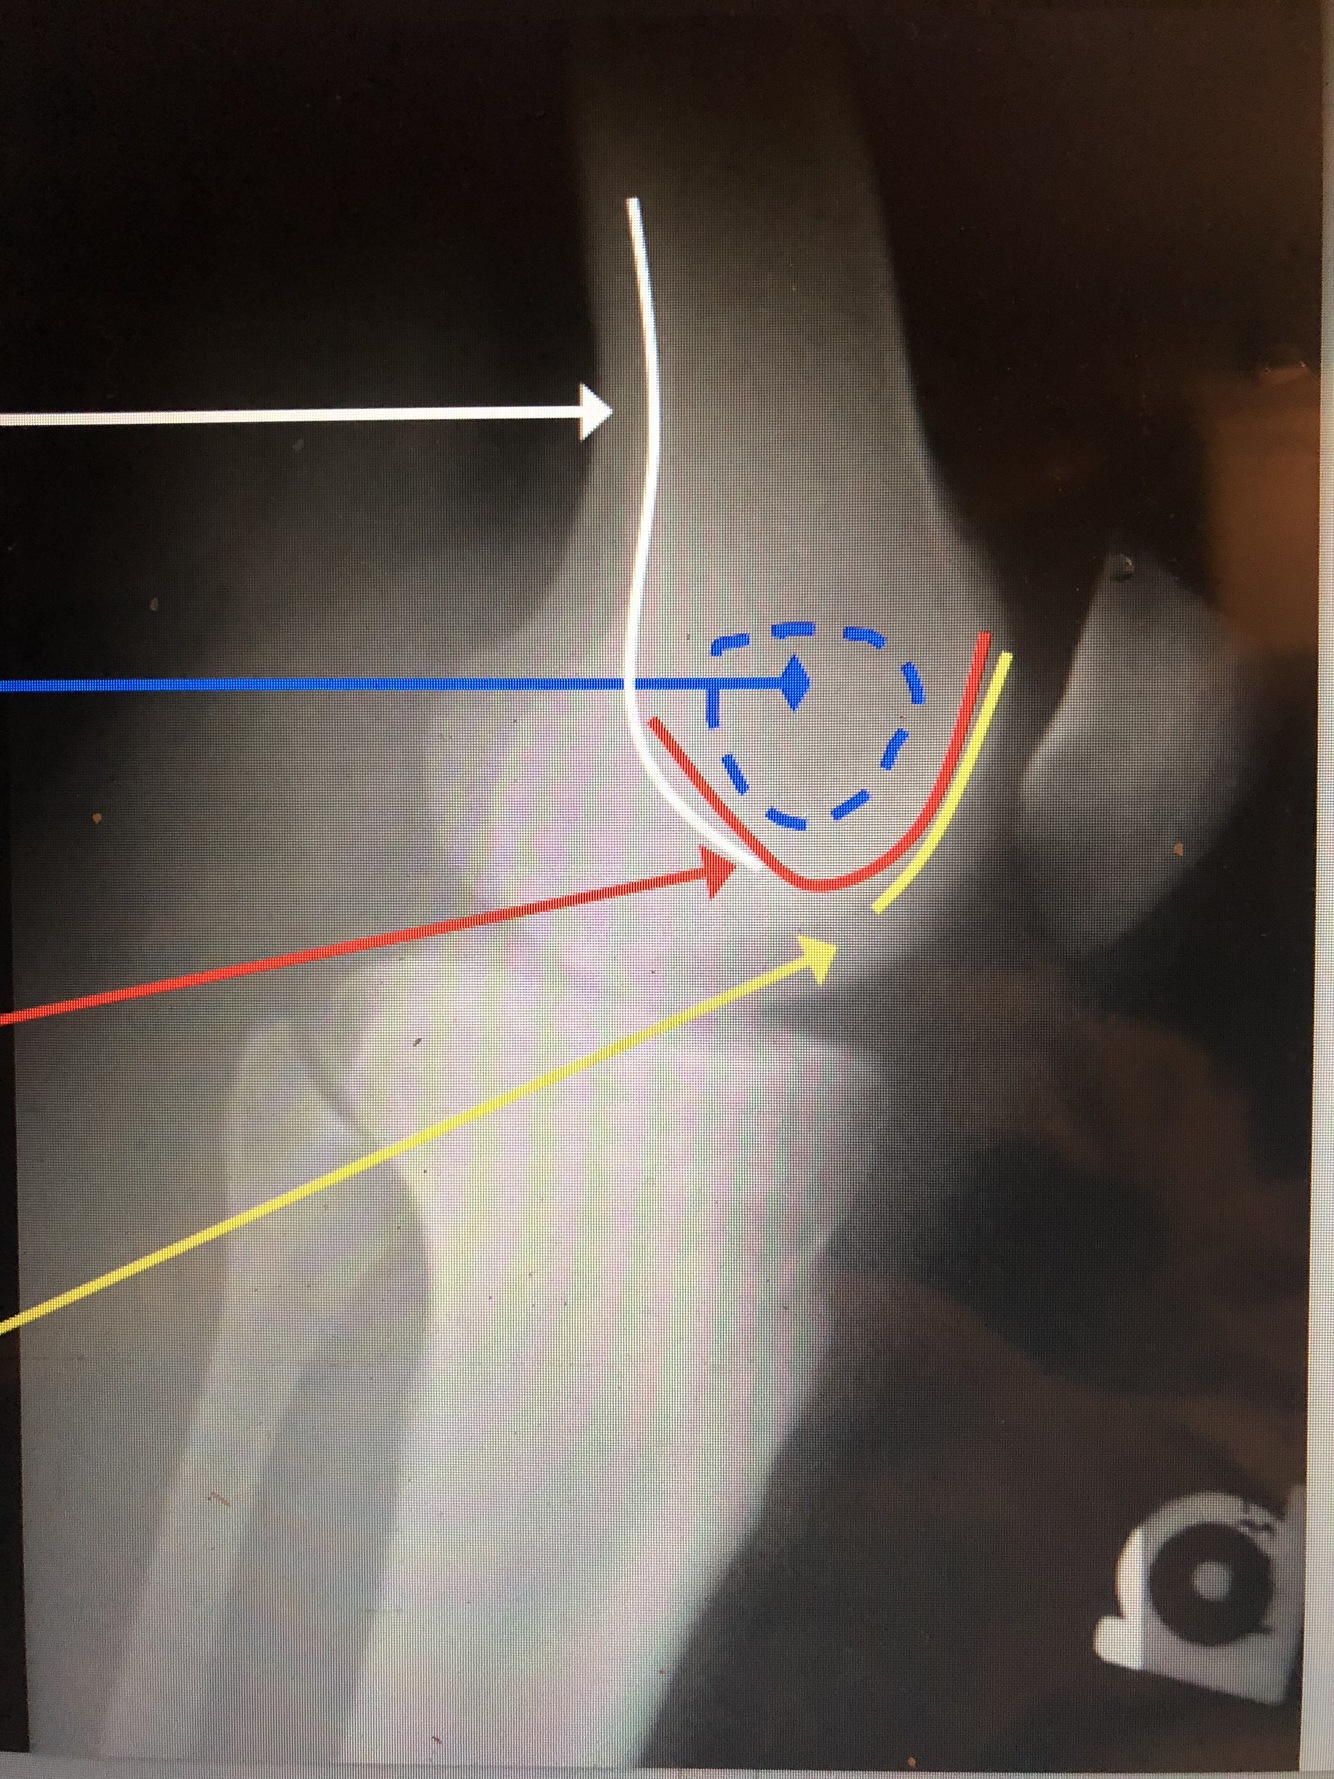

Q

Popliteal Surface of the Femur

17

What is the blue dotted lines?

Ludloff’s Spot – area of lucency in condyles

Intercondylar Notch/Groove

Patellar Surface of the Femur

patella